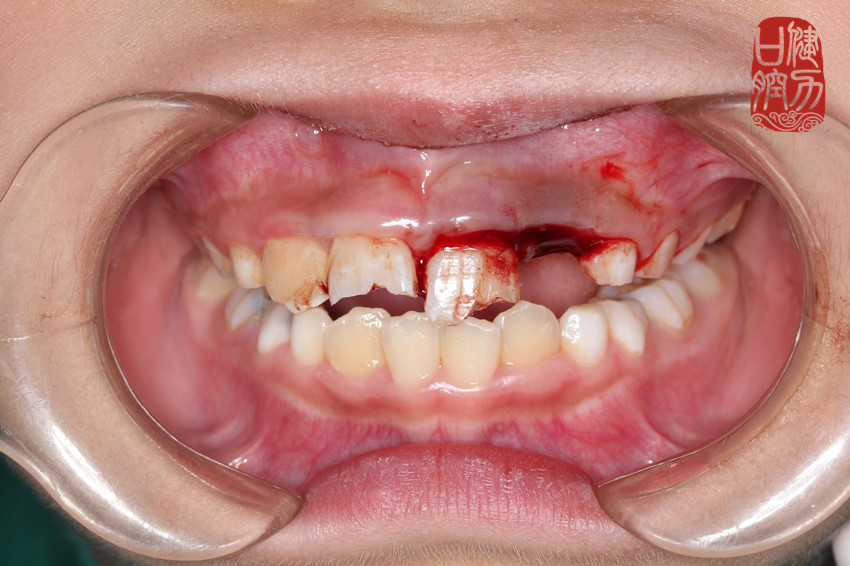

(儿童牙外伤的案例)

No.2 牙折断

牙折分为冠折、根折、冠根联合折。

牙折断后需要拍受伤牙的牙片,看牙根是否折断。缺损局限于釉质、牙本质,牙髓未暴露者,可以使用复合树脂行美学修复。如果伤及牙髓,就需要即刻保护牙髓,甚至需要去除牙髓做根管治疗。如果伤及牙根,则需要根据折断部位的不同,选择做根管治疗后固定患牙或拔除患牙。

牙折断不仅会影响前牙的的美观,更有可能会伤及牙髓,需要即刻保护牙髓,治疗原则是尽量保持患牙,恢复牙体外形与功能。